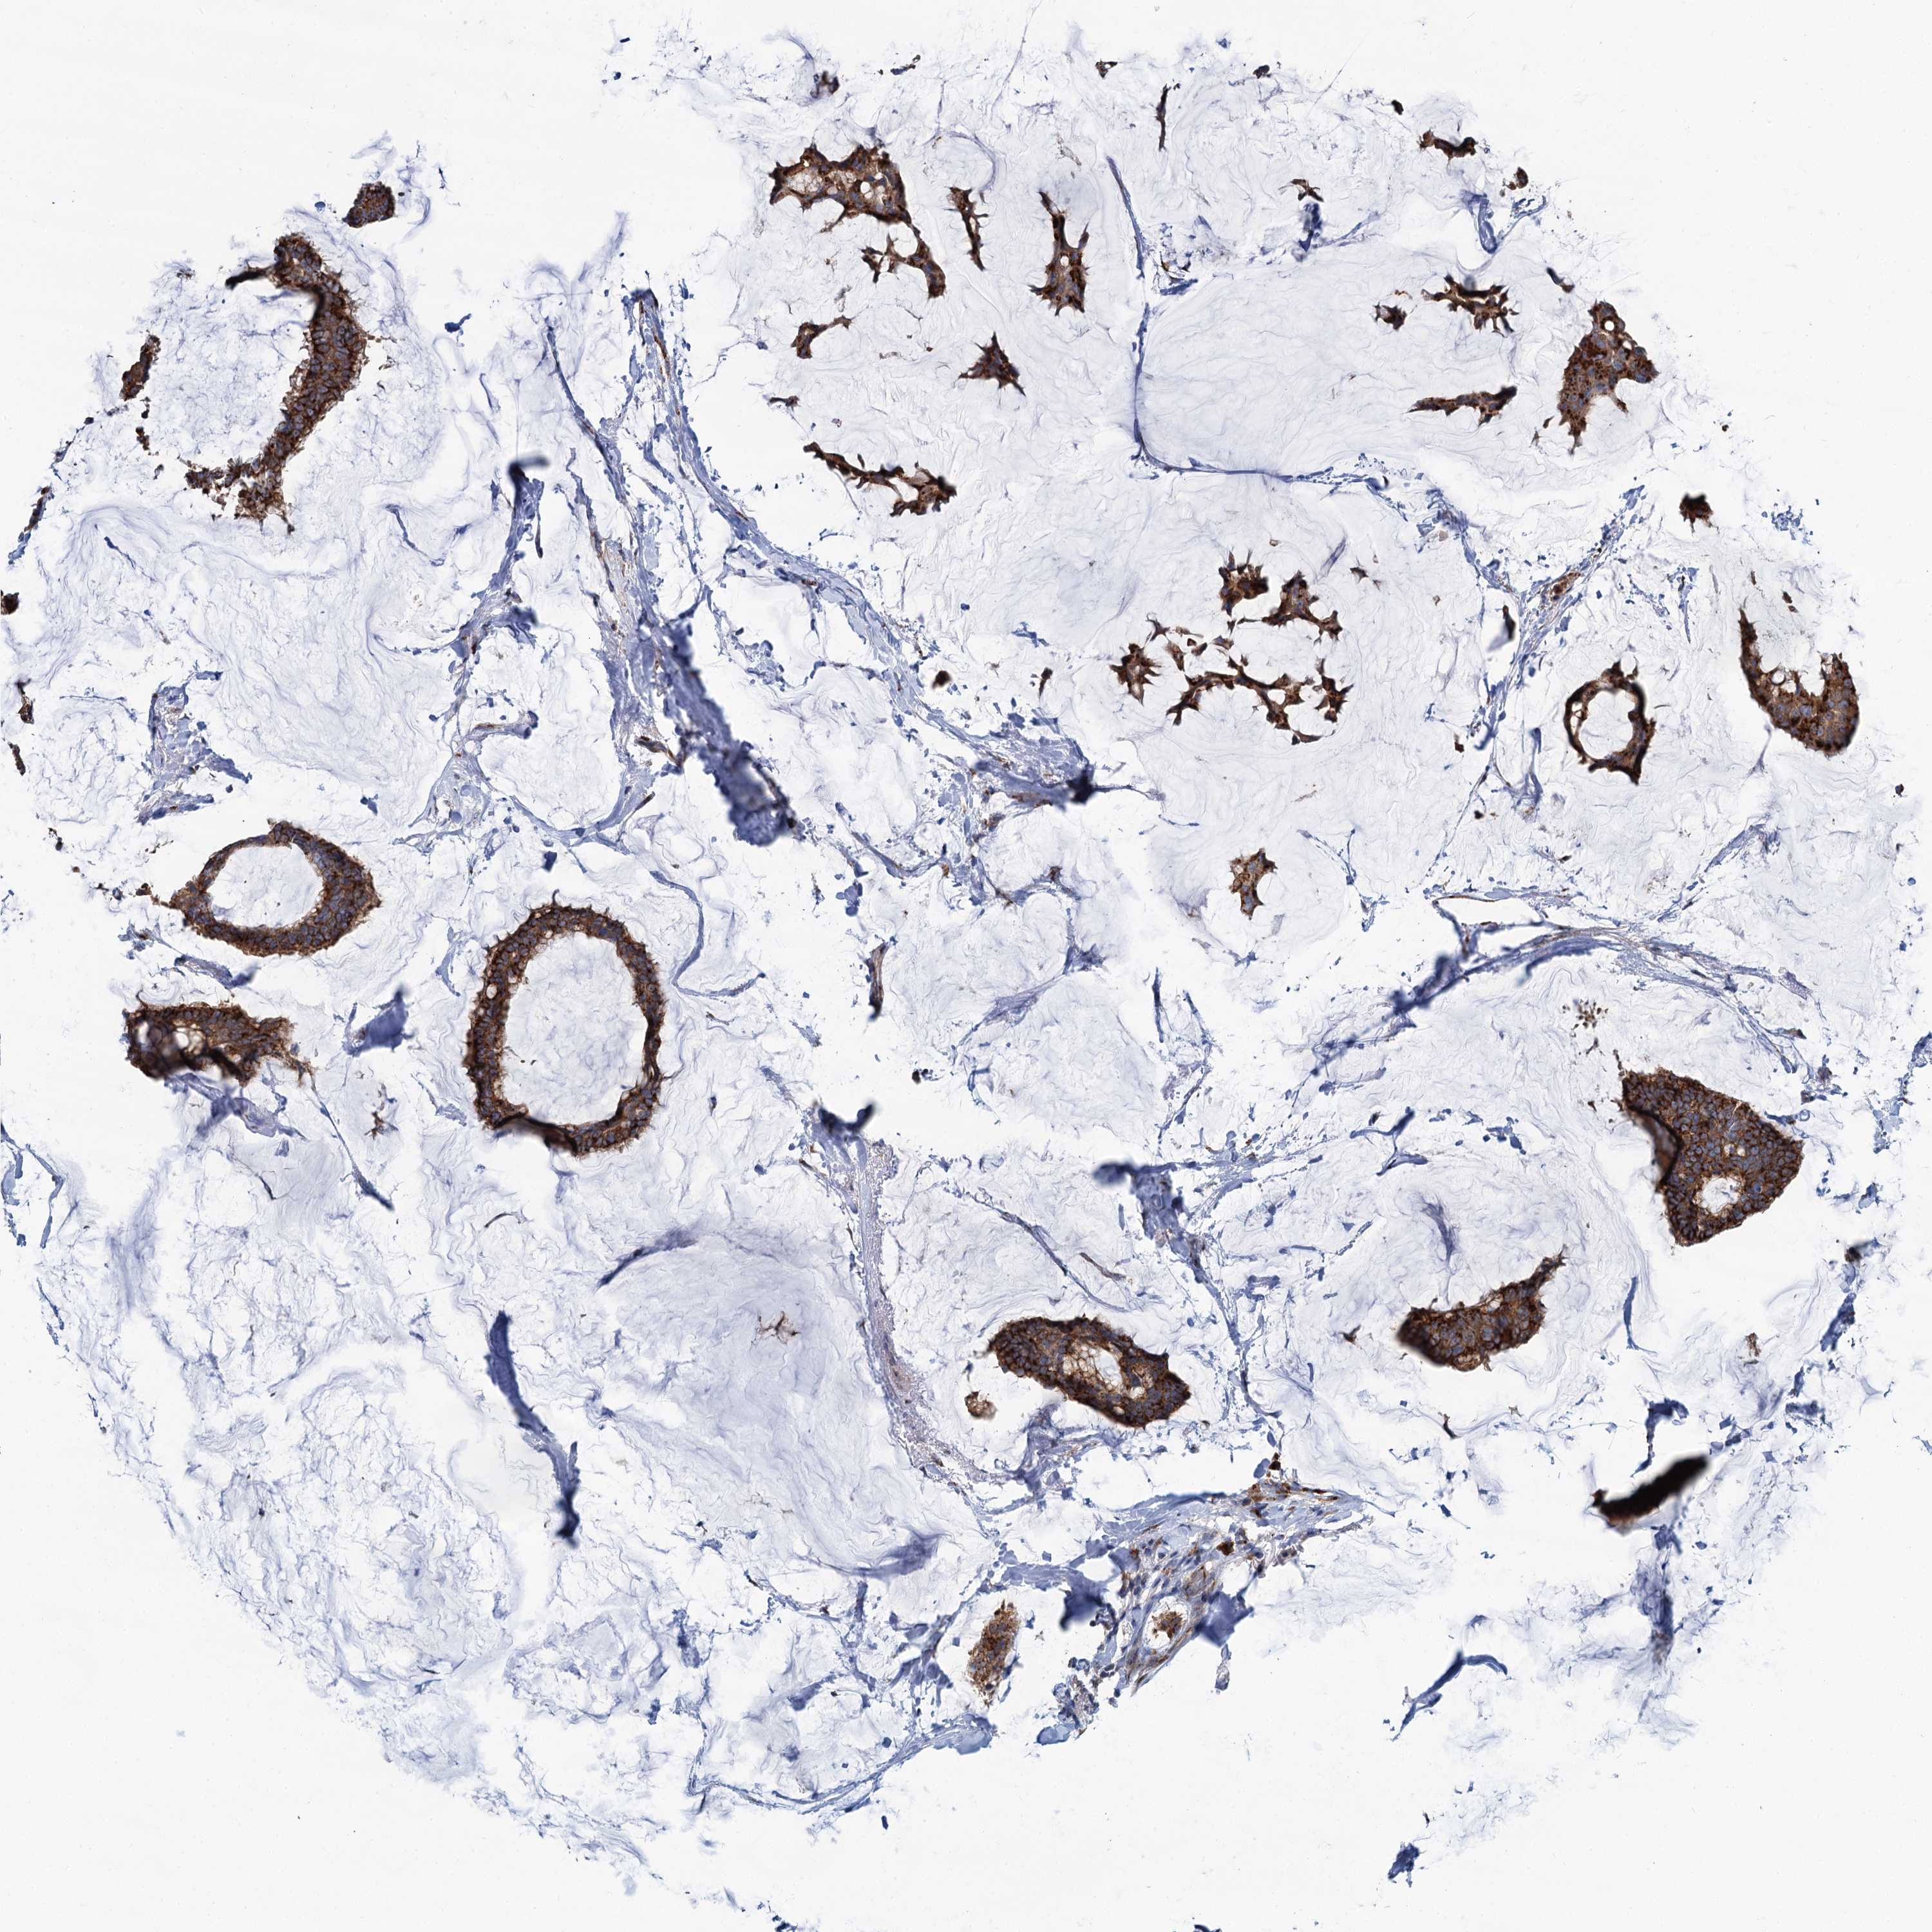

CANCER BREAST CANCER Show tissue menu

BRCA TCGA BRCA VALIDATION PROTEIN EXPRESSION

Breast cancer

Human cancer